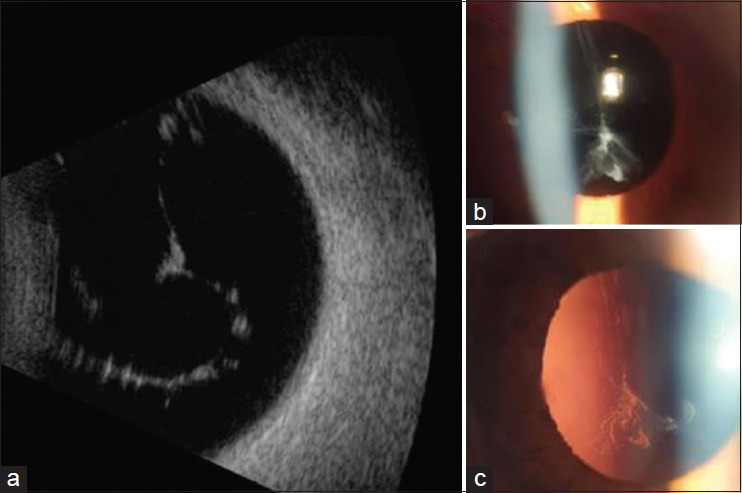

Results: Genetic evaluation demonstrated the presence of a novel pathogenic variant NM_001854.4: C.3168+1G>A (chr1:102961865-102961865), in the intronic region that follows exon 41 of the COL11A1 in the three affected members of the family. This variant is located 1 base from the natural splicing region of this exon and consequently can impact intron removal and protein formation. As for the ophthalmological findings, the presence of low visual acuity, high axial myopia, and pathological vitreous gel with a "beaded" appearance was observed in the index case. Further clinical examination showed that other family members also had vitreous and retinal degeneration.

Conclusions: A heterozygous novel pathogenic variant in COL11A1 was identified by complete genome sequencing in a Brazilian family with STL. Ocular examination findings photographically presented confirm the characteristic features of STL type 2.